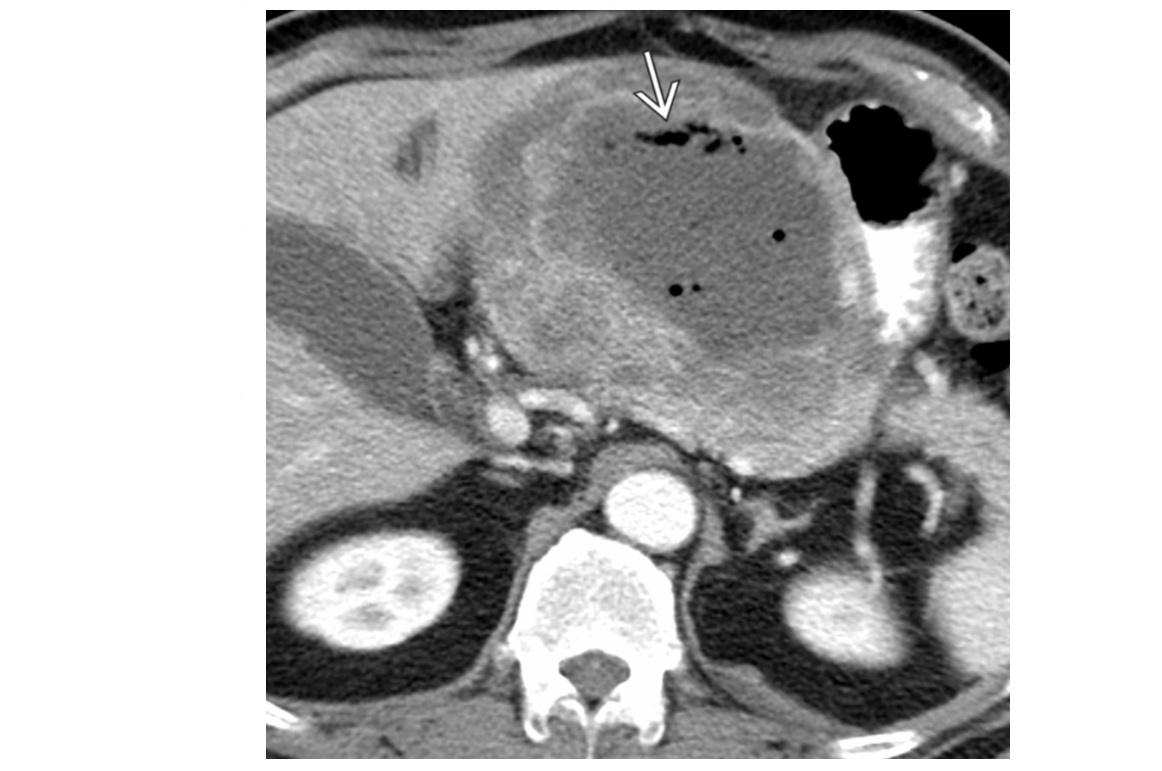

Pseudomyxoma peritonei Low-attenuation masses (usually < 20 HU) scattered throughout peritoneum Thick walls, septa and calcificaiton 'scalloped appearance'/displace of liver and spleen **Mucocele** Dominant cystic or solid mass often present in right lower quadrant/tip caecum (in expected location of appendix) . +/- curvillenar calcifcation Mucin-producing neoplasm of appendix causes appendiceal distention and subsequent perforation with diffuse intraperitoneal spread of mucinous implants DDx Peritoneal carcinomatous - discrete tumour Implants are solid -Rarely may cause "scalloping" TB peritonitis - Ascites and omental/mesenteric fat stranding with symmetric, smooth enhancement and thickening of peritoneal lining -can be loculated - look for including low-attenuation mesenteric nodes and thickening of cecum and terminal ileum